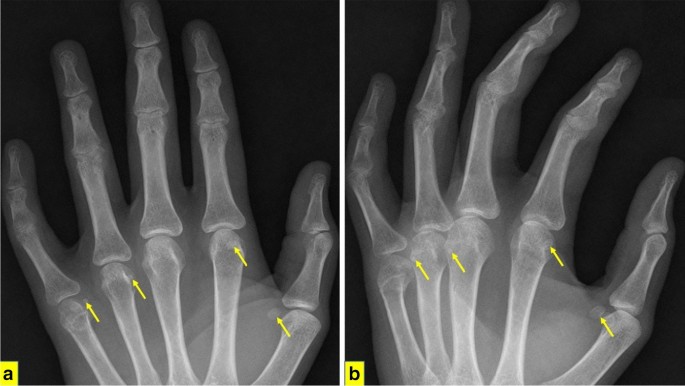

Sesamoid Bone X Ray Collection 2022 Sesamoid Bone X Ray Collection 2022

Sesamoid Bone X Ray

Sesamoid fracture | Radiology Reference Article | Radiopaedia.org Radiology Review - Sesamoid fracture | Axis Sports Med Toes (sesamoid view) | Radiology Reference Article | Radiopaedia.org Sesamoid | Radiology Reference Article | Radiopaedia.org Sesamoid bone - Wikipedia Sesamoid Bone X Ray